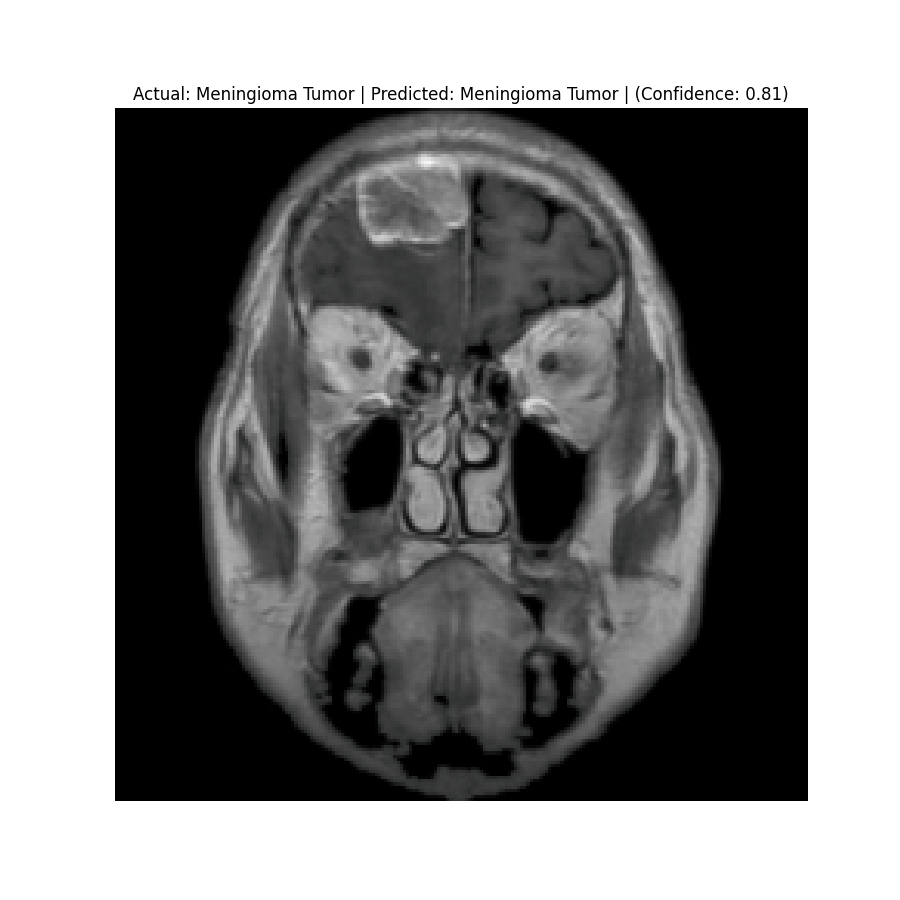

The dataset used in this project is the Brain Tumor Classification (MRI). It consists of MRI scans categorized into four classes: 👇

Glioma Tumor | Meningioma Tumor |

Normal | Pituitary Tumor |

Results

Check the predictions in the predictions folder. Below are some sample results:

![]() Actual: Meningioma Tumor Predicted: Meningioma Tumor (Confidence: 1.00) | ![]() Actual: Meningioma Tumor Predicted: Meningioma Tumor (Confidence: 0.81) |